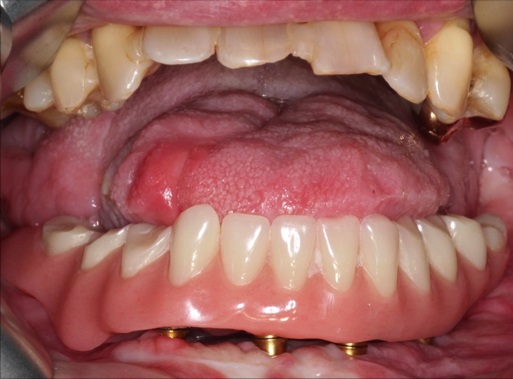

Postoperative imaging confirmed minimal intersegmental gaps to the mandibular remnants with undisturbed healing but limited overall bone volume (Fig. 7a-c). Therefore removal of the PSPMP and a preimplantological augmentation with corticocancellous iliac bone grafts followed 16 months later.

Finally, dental implants were inserted (Fig. 8).